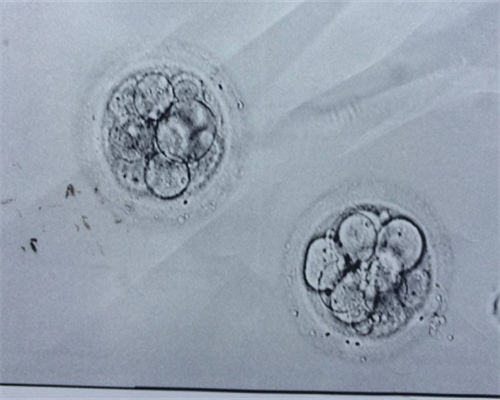

移植过程比较快的,也不会有什么痛苦的感觉,移植前会进行一次信息确认如图